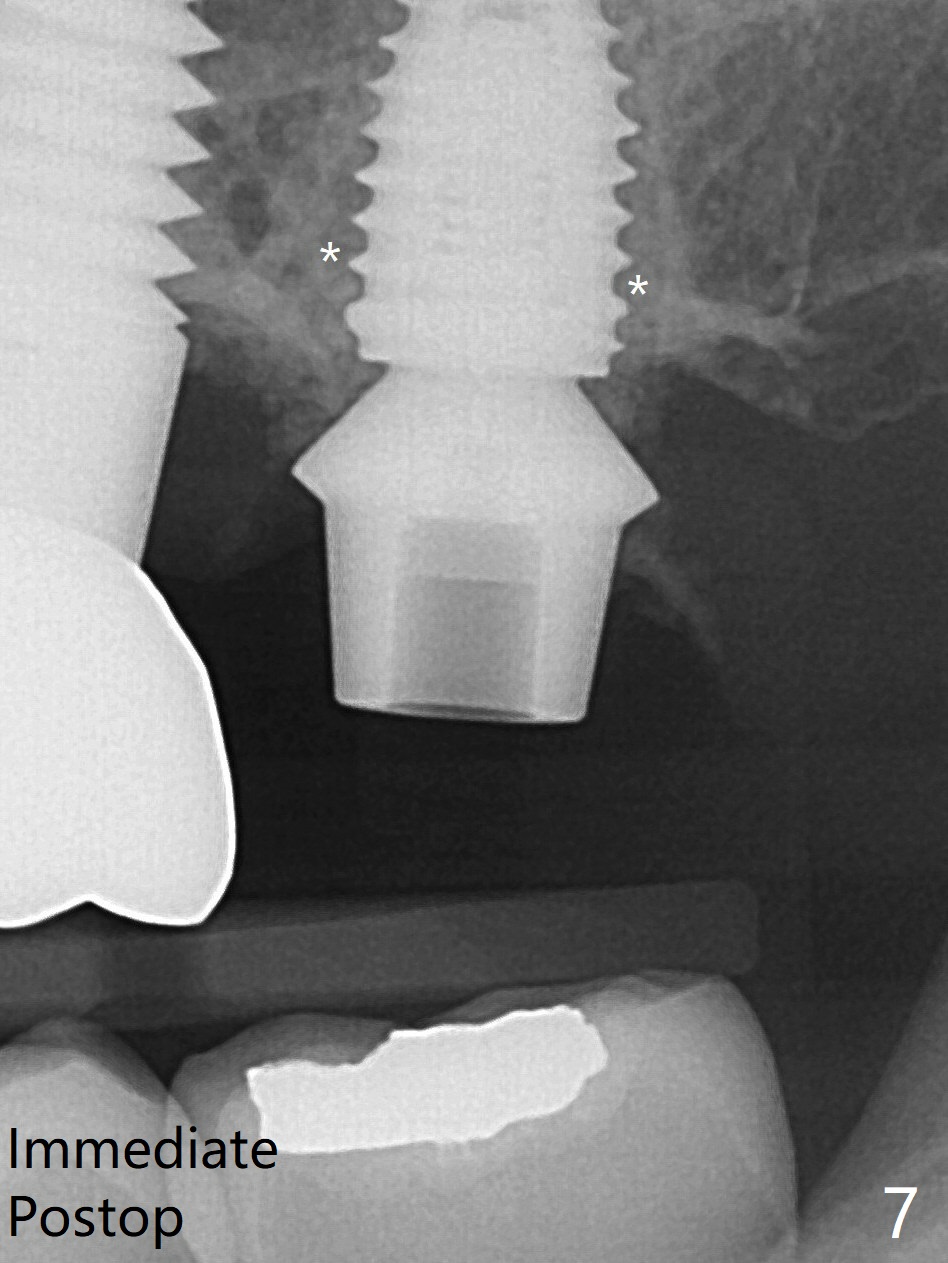

术前15号牙远中隐裂(图一:^),14号牙植体光滑面腭侧暴露(8年前腭侧窝植入),但是牙龈健康(图二)。14号牙牙槽窝没有肉芽组织,利用导板(Shinning Oral Scanner)完成3.5毫米钻洞,无法使用圆钻做内提升,改用4x10毫米报废植体提升,不幸窦膜好像破裂(因为薄),塞入半块PRF膜,促进修复,然后使用4.5x10毫米报废植体扩大植牙床(图三,四),无意达到部分提升(*),取出报废植体,发现植牙床没有穿孔了,加入少量粘性骨粉(图五:S(即使在窦内不容易分散))后,植入正式植体和基台。植体周围间隙(图五:*),使用刮匙,牙周探针,和长探针(图六)将骨粉输入深部(图七:*)。